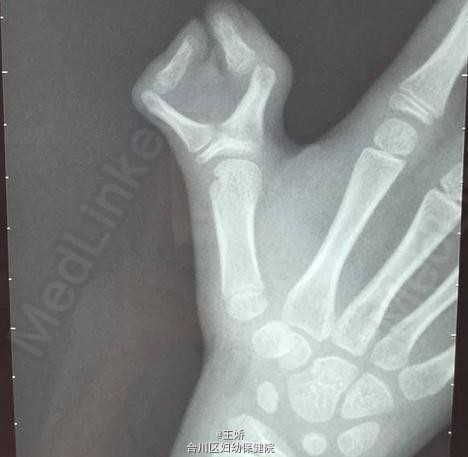

左拇指多指畸形伴指间关节脱位

患儿9岁、女,左拇指多指畸形伴指间关节脱位9年。平素体质一般,无药物、食物过敏史,无高血压、心脏病等系统病史。

X线检查骨质情况

于今日行左拇指多指切除、关节复位、截骨矫正克式针内固定、关节囊修补术。